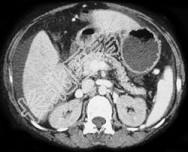

- 单项选择题如图,银染色可见系膜区及毛细血管袢有淀粉样物质沉积, 刚果红染色呈砖红色阳性,电镜以淀粉样纤维沉积为特点, 其病理诊断可考虑为 ( )